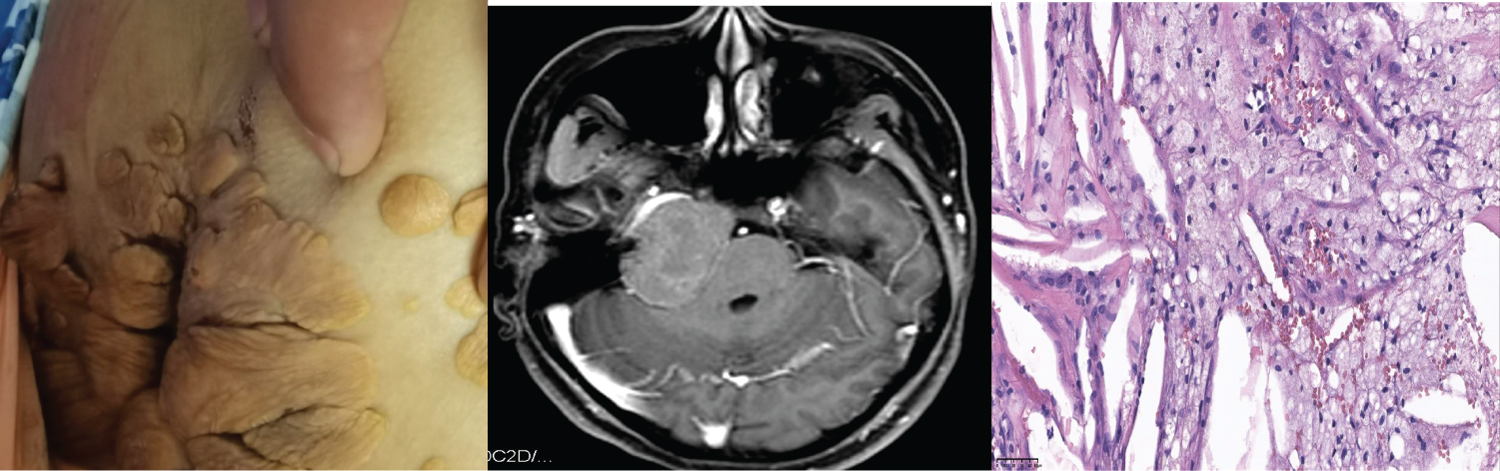

A 25-year-old female complained of right-sided facial paralysis and hearing loss for 4 years, and an intracranial mass was found for 1 week. The patient had a history of FH and excision of the left elbow mass; positive sign: The right eye is incompletely closed, the right frontal lines and nasolabial fold become shallow, right ear hearing loss, multiple masses are seen in the skin of the right popliteal fossa, sacral caudal (Figure 1a), and right elbow; MRI showed: Right middle posterior skull base mixed density mass; Focal bone destruction (Figure 1b); cholesterol (TC): 14.9 mmol/L, low-density lipoprotein (L-DL) 12.87 mmol/L, After admission, ezetimibe was taken orally to reduce blood lipid. All tumors were removed by retrosigmoid sinus approach under electrophysiological monitoring. Postoperative pathological report: Xanthoma (Figure 1c).

Figure 1: a) Xanthomas on the skin of the sacrococcygeal; b) MRI showed the skull base has long T1 and long T2 lesions on the right side of the middle straddle, with flair showing mixed signals; local bone destruction in the lesion; c) Fibrous tissue hyperplasia with abundant cholesterol fissures, Foam cell aggregation with necrosis and calcification (× 40). View Figure 1